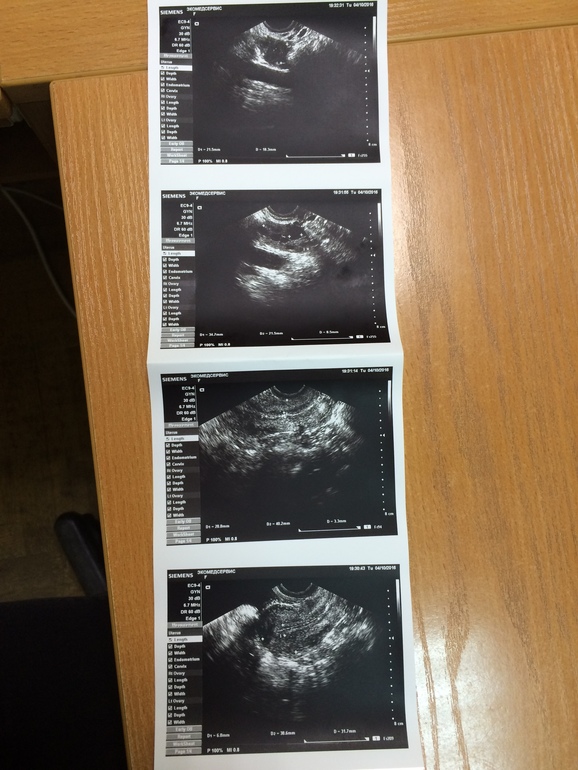

Верхнее фото какого яичника? Не могли бы увеличить? Киста - это образование от 30мм, поэтому перепутать сложно. Фолликул вырастает максимум до 25-26мм.

Теперь вижу. Я бы не говорила о мелкокистозной структуре, но левый яичник имеет кистозную трансформацию, то есть видны только фолликулы, при отсутствии достаточного количества ткани яичника. Если врач говорит о кисте 9мм, то это никак не функциональная киста. Это либо фолликул, либо, если врач считает, что это не фолликул точно, то должен предположить кисту параовариальную, к примеру, но не подходит ее распопложение, либо эндометриоидную, но строение иное, либо должен сказать о кисте в стадии регресса, но для этого он должен знать, что на этом самом месте ранее была киста больших размеров.

И в заключении написали что функциональные кисты до 9 мм, а везде указано что кисты должны быть больше